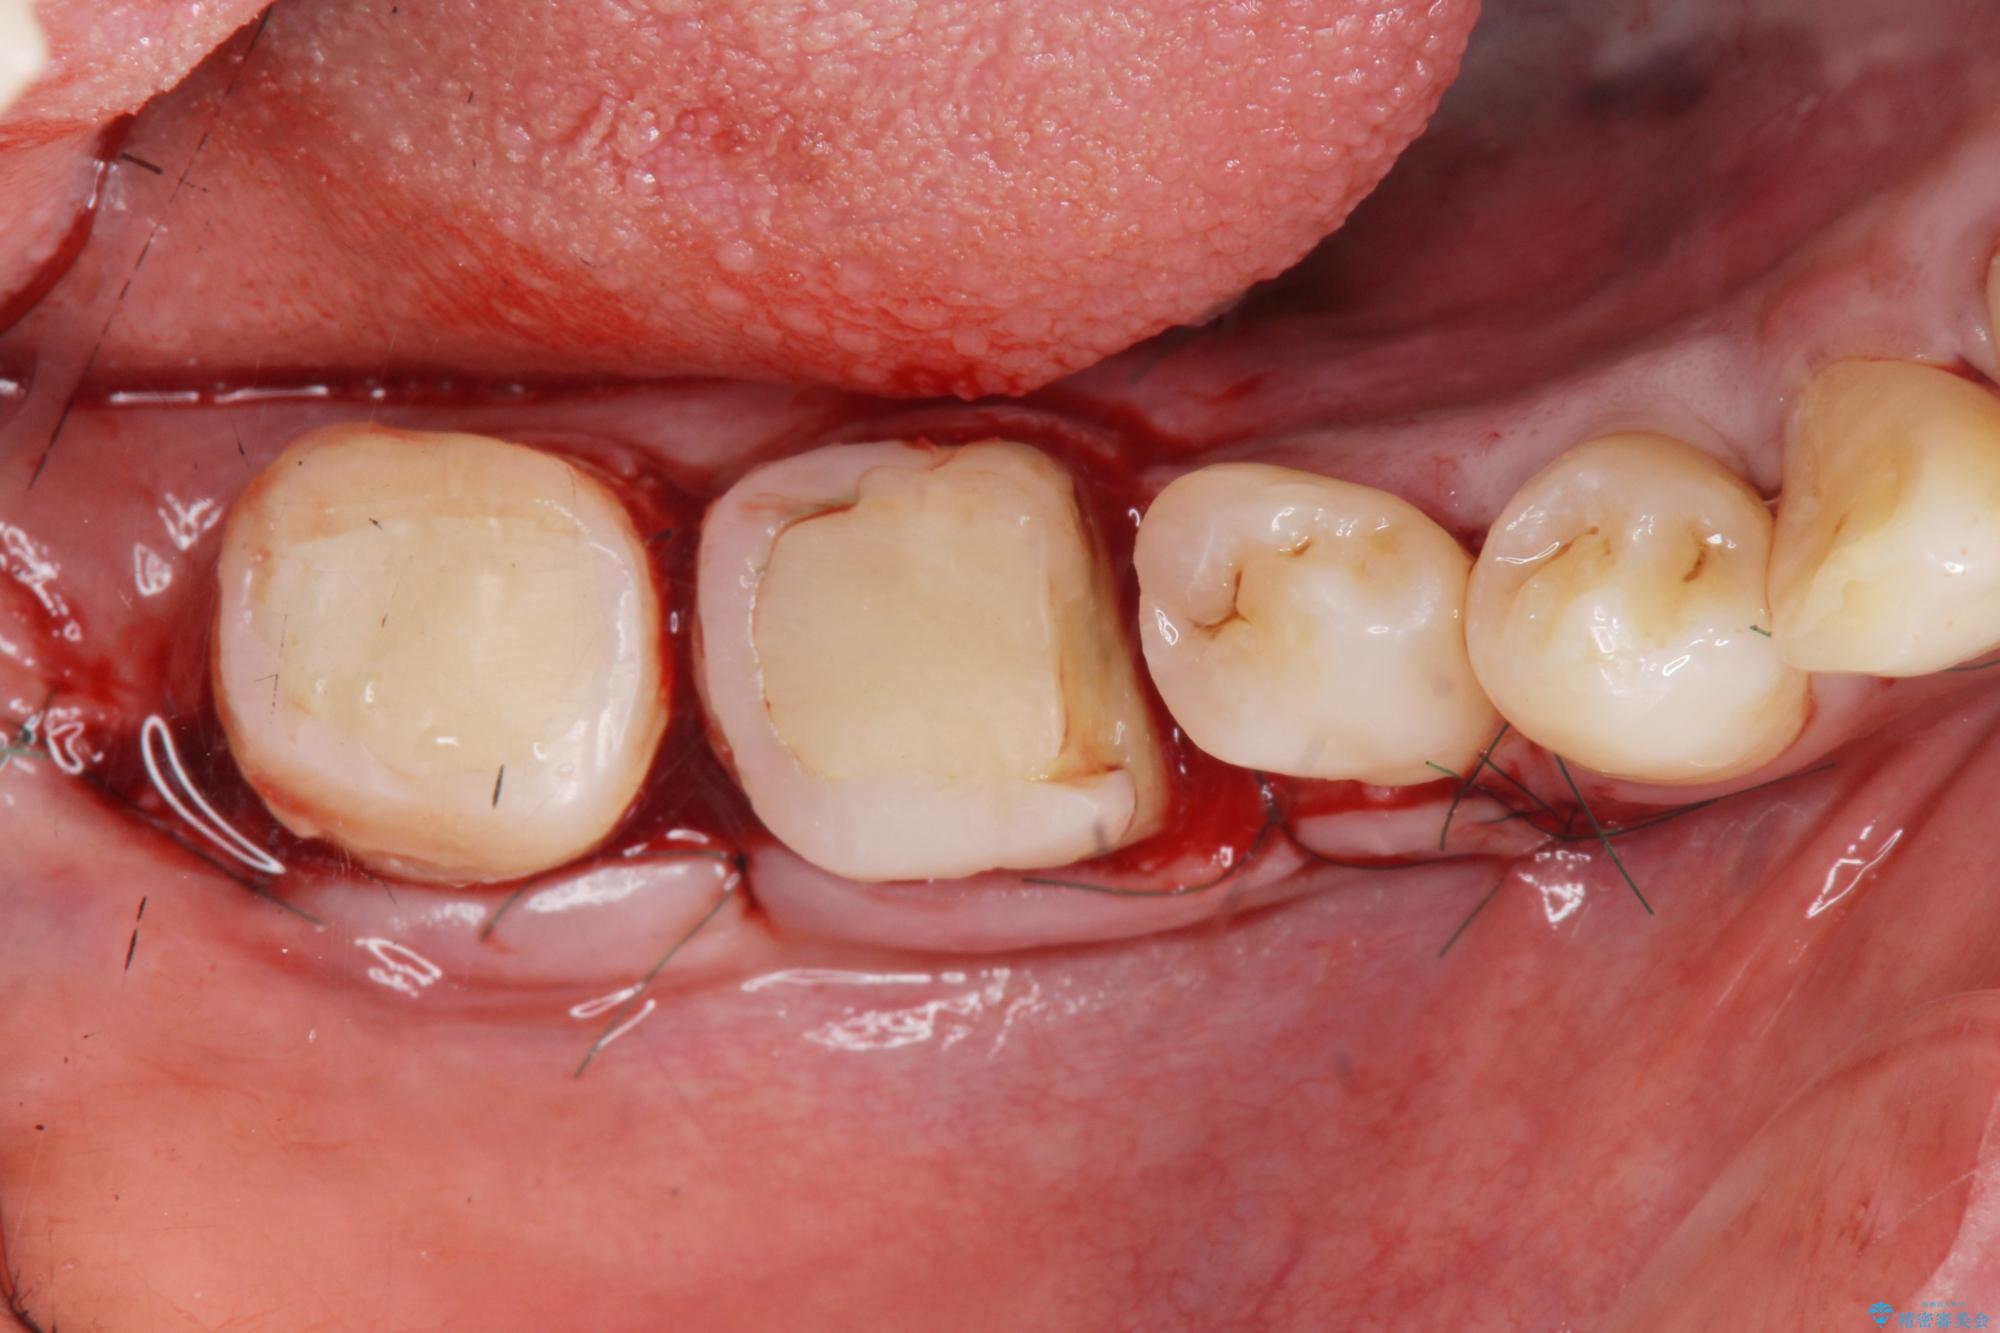

奥歯は既に根管治療が為されクラウンを装着する必要性がある状態ですが、歯の高さが低くクラウンの安定性・強度を担保するために歯周外科を行う治療計画としました。

歯周外科を行うことで、歯ぐきの位置を下げ歯の高さを作り出し安定したクラウンの装着が可能となります。また同時に舌の邪魔となっていた骨隆起の除去を行うこととしました。

歯周外科に際しては、静脈内麻酔を行うことでほとんど記憶のないうちにリラックスした状態で受けていただくことができました。